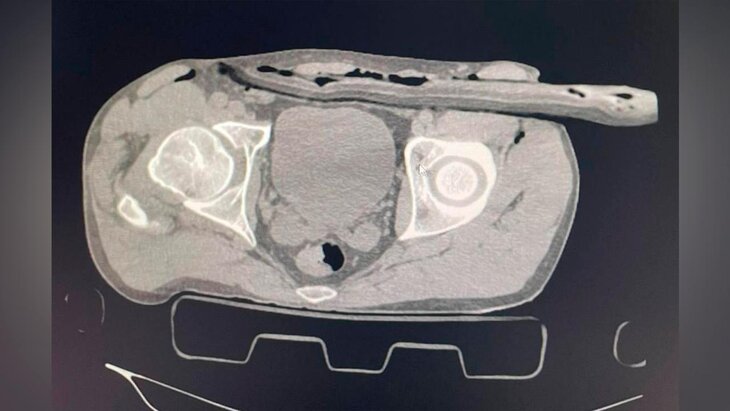

Фото: телеграм-канал "Разборчивым почерком"

Пострадавший ремонтировал крышу загородного дома без страховки и упал на сук. Ветка прошла через бедро в толщу брюшной стенки. В больнице ему сделали компьютерную томографию и УЗИ, которые показали наличие свободной жидкости в животе.

Врач-хирург Солнечногорской больницы Иван Балычев отметил, что ветка не задела важные артерии и органы брюшной полости. В ходе операции, которая длилась около часа, медики ушили дефект в брюшине, провели ревизию органов брюшной полости, а также сделали дренаж раневого канала.